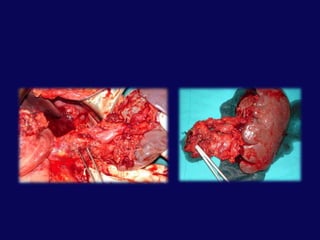

Pankreas travması: PankreatikoduodenektomiendikasyonlarıPankreas başından ve/veya yandaş damarsal yapılardan  masif, kontrol edilemeyen kanamaPankreas başında masif ve rekonstrükte edilemeyecek duktal yaralanmaRekonstrükte edilemeyecek kombine yaralanmalar:Duodenum ve pankreas başıDuodenum, pankreas başı ve koledok

HepatoduodenalligamanPankreasDuodenum 2. kıta

PortalvenSMV

Portal venKoledokSplenik venDudenumSMVPankreas başı